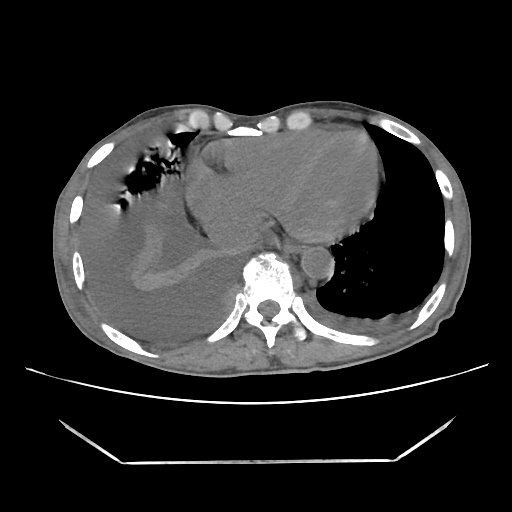

A 56 years old man with